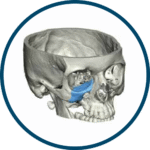

OMNIPORE® de Matrix Surgical es un implante poroso de alta densidad diseñado para reconstrucción cráneo-facial y cirugía estética. Fabricado en polietileno poroso, permite ser fresado, cortado o moldeado durante la cirugía para una adaptación precisa a la anatomía del paciente. Su estructura favorece el crecimiento tisular, promoviendo una mejor integración y estabilidad a largo plazo. Se suministra estéril y listo para su uso inmediato, evitando riesgos de contaminación al no requerir reesterilización.